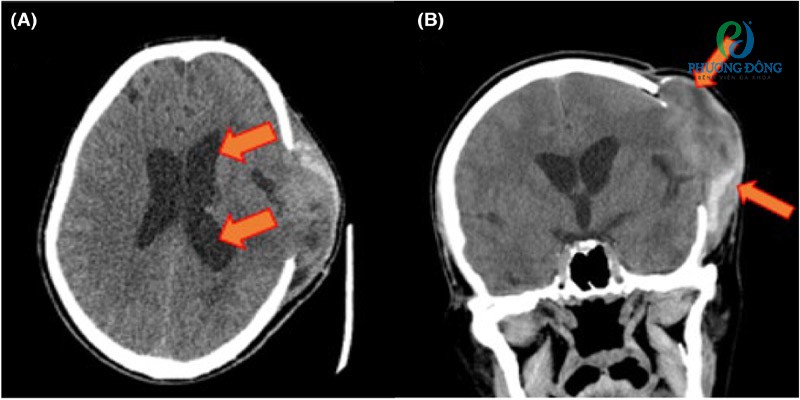

• Chụp CT (cắt lớp vi tính): CT sử dụng tia X kết hợp xử lý vi tính để tạo hình ảnh chi tiết não bộ dưới dạng lát cắt 2D hoặc tái tạo 3D. Kỹ thuật này giúp bác sĩ nhanh chóng đánh giá tình trạng xuất huyết, khối máu tụ, phù não cũng như mức độ dịch chuyển mô não – những yếu tố thường liên quan trực tiếp đến thoát vị não.

Hình ảnh chụp cắt lớp vi tính (CT) nãoHình ảnh chụp cắt lớp vi tính (CT) não theo mặt phẳng trục (A) và mặt phẳng vành (B) cho thấy tình trạng não úng thủy và thoát vị não qua lỗ hổng sau phẫu thuật mở sọ.

• Chụp MRI (cộng hưởng từ): MRI hoạt động dựa trên từ trường và sóng điện từ, cho phép tái tạo hình ảnh cấu trúc não với độ phân giải cao. Đây là phương pháp có độ nhạy vượt trội, giúp phân biệt rõ mô não bình thường và mô tổn thương, từ đó hỗ trợ xác định chính xác dạng và vị trí thoát vị não.